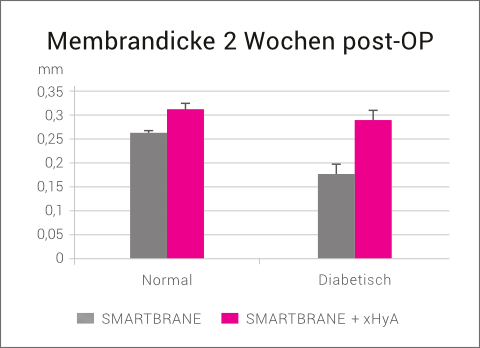

- Verlängerung des Membran-Abbauprofils

Darüber hinaus verlängert vernetzte Hyaluronsäure das Abbauprofil von Kollagenmembranen. In einer Tierstudie mit gesunden und diabetischen Ratten wurden native Kollagenmembranen (SMARTBRANE) in eine subkutane Tasche implantiert und der Einfluss von xHyA auf den Resorptionsgrad der Membranen nach 2 Wochen post-OP untersucht. Die vorherige Behandlung mit xHyA führte zu einer signifikanten Verringerung des Abbauprozesses, insbesondere bei den diabetischen Ratten, vermutlich aufgrund der xHyA-induzierten Herabregulierung der Makrophagenaktivität.25